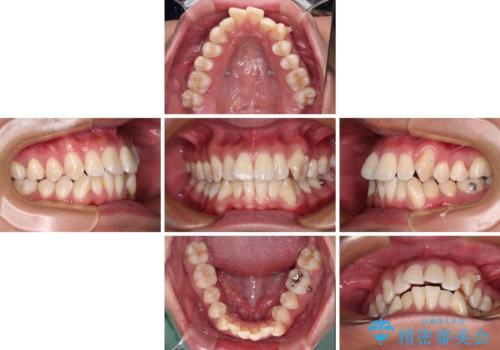

- 八重歯と飛び出している前歯を気にして来院された患者様です。

歯列としてはインビザラインでもワイヤー矯正でも対応できるものでしたが、上顎の八重歯や下顎小臼歯の捻転といったインビザラインでは時間のかかってしまう歯列不正が認められたため、補助装置やワイヤー矯正を治療当初に使用することで、インビザラインによる治療をスムーズに行えるように計画しました。